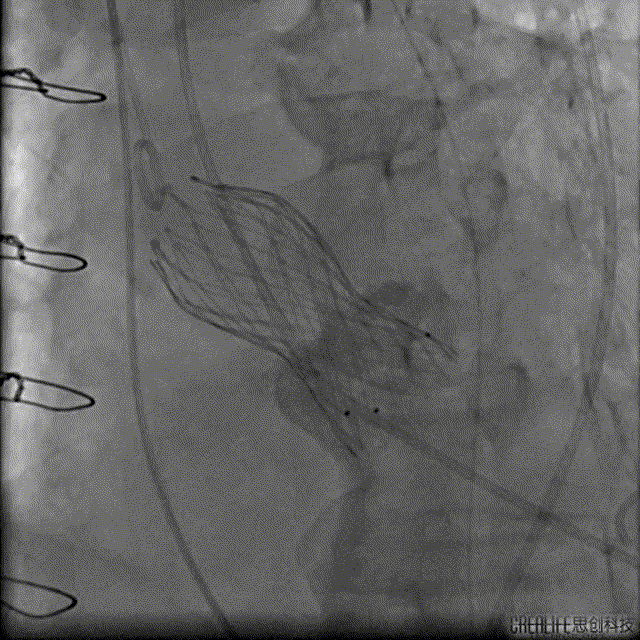

解剖上,这个患者虽然是右无融合的二叶瓣,但是右窦发育较小,形态上接近0型二叶瓣,瓣上钙化中,且集中在左窦,接近左右瓣叶联合部。瓣环及流出道平面较大,而瓣上结构较小,瓣叶联合部距离只有26,这种情况下只能考虑根据瓣上结构进行选择瓣膜。目标瓣膜为26号,为了避免破坏瓣上结构,我们选择26瓣膜的下限20号瓣膜进行与扩张。因为主动脉弓和升主动脉角度问题,没有选择plus。20球囊扩张可以看到左窦钙化很硬,右无联合可以推开,没有反流,故选择26号瓣膜,高位释放。释放后瓣膜下滑到标准位,有明显的腰,故用20球囊进行后扩展。最后造影虽然有中度瓣周漏,但是考虑患者狭窄解除,且升主动脉人工血管限制了瓣膜的流出端,未再行瓣中瓣。术中撤除ECMO,辅助循环约1小时。

手术过程:

Numed20后扩